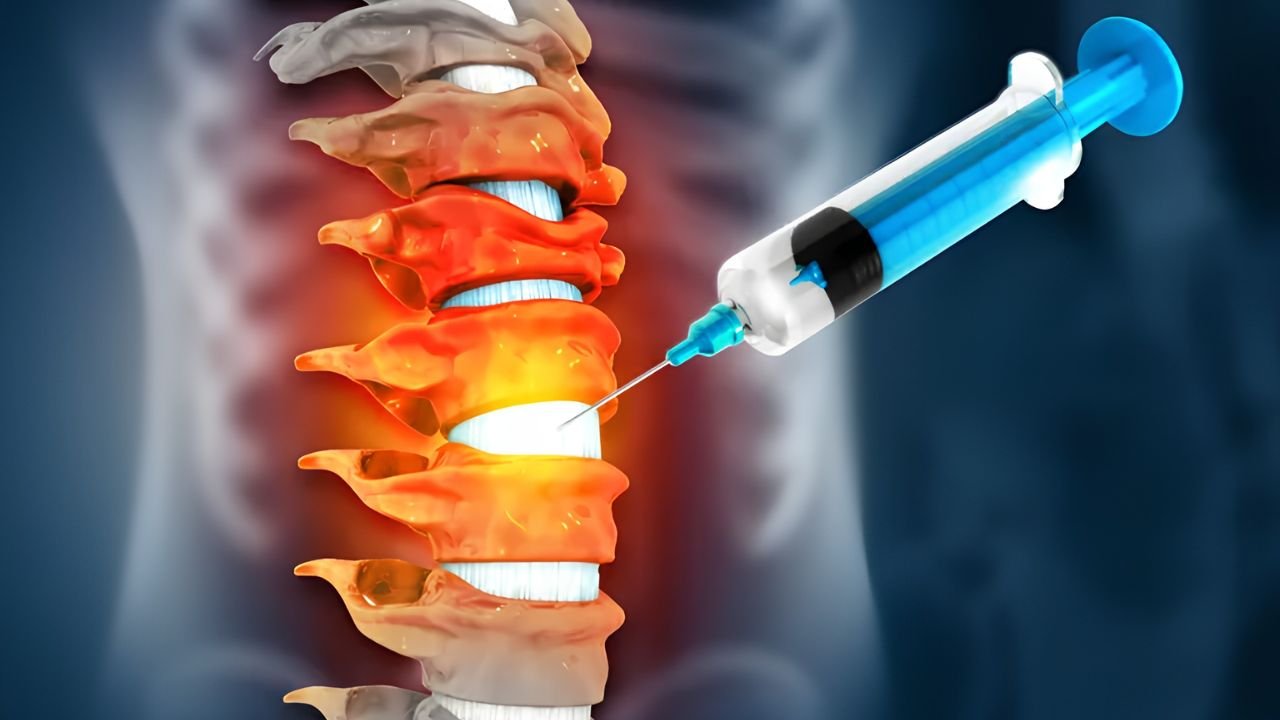

Não. Nossa filosofia prioriza procedimentos minimamente invasivos. A grande maioria dos casos é resolvida com intervenções percutâneas (sem cortes), terapias medicamentosas ajustadas, ondas de choque ou infiltrações guiadas. A cirurgia é considerada apenas quando estritamente necessária.

São técnicas onde utilizamos ultrassom ou radioscopia em

tempo real para guiar agulhas e instrumentos com precisão milimétrica até o alvo da dor. Isso garante maior segurança e eficácia.

O conforto do paciente é prioridade. Os procedimentos são realizados com anestesia local e, quando necessário, sedação leve. A maioria dos pacientes relata alívio imediato ou desconforto mínimo durante a aplicação, retornando às suas atividades em pouco tempo.